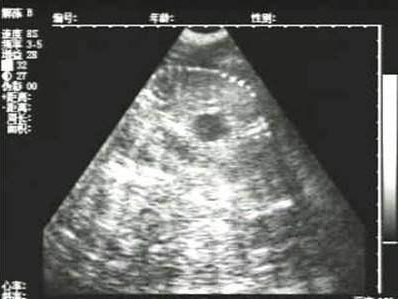

豬用B超機(jī)檢測(cè)有胎兒圖像

需要注意的是,出現(xiàn)云團(tuán)狀必須雙側(cè)檢查加以確認(rèn).根據(jù)B超機(jī)顯示圖我們大致可以判斷孕齡.圖像呈橢圓或者卵圓形大致為30天左右孕齡;圖像呈橢圓形或者卵圓形外,有明顯發(fā)亮骨骼圖像大致為50孕齡左右;圖像囊胚消失,發(fā)亮處隱約可見(jiàn)竹節(jié)狀東西為成型胎兒骨骼,一般為后期80孕齡以后。一般B超機(jī)成像會(huì)出現(xiàn)三種顏色,白色、黑色、灰色。白色為密度較高的物體,如骨骼或者結(jié)實(shí).黑色一般為液體,包括血液、羊水、組織間隙液體、炎癥病灶等?;疑话銥閷?shí)質(zhì)性物質(zhì),如肌肉。